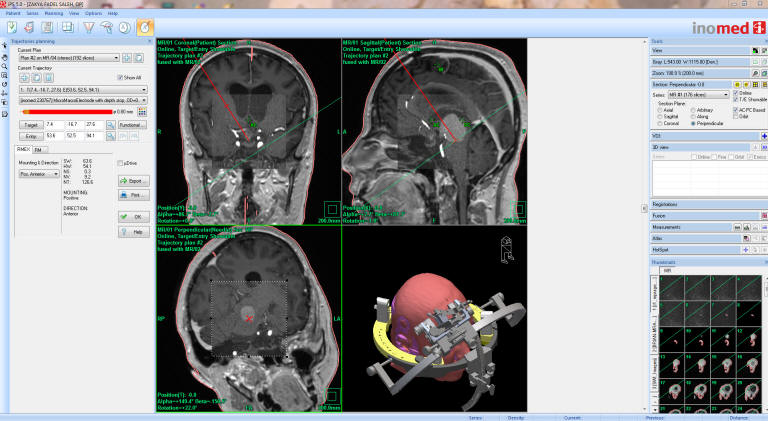

In another case with patient operated by me 14-November-2006 for huge craniopharyngioma through subfrontal approach with mobilization and preservation of the olfactory tracts. The patient then developed recurrence and was operated by me 26-May-2015. During the second surgery an Ommaya reservoir must be directed from a point without violating the vascular structures and the CSF to avoid contamination. The following figures (8-13) showing the case:

Fig-9: The ceramic ring fixed with localizer and sent to MRI with TxRx head coil to perform coordinated data to the iPs 5 planning software.

Fig-10: The trajectory was exactly planned to have the tube in the most dependant point of the cyst without contaminating the CSF.